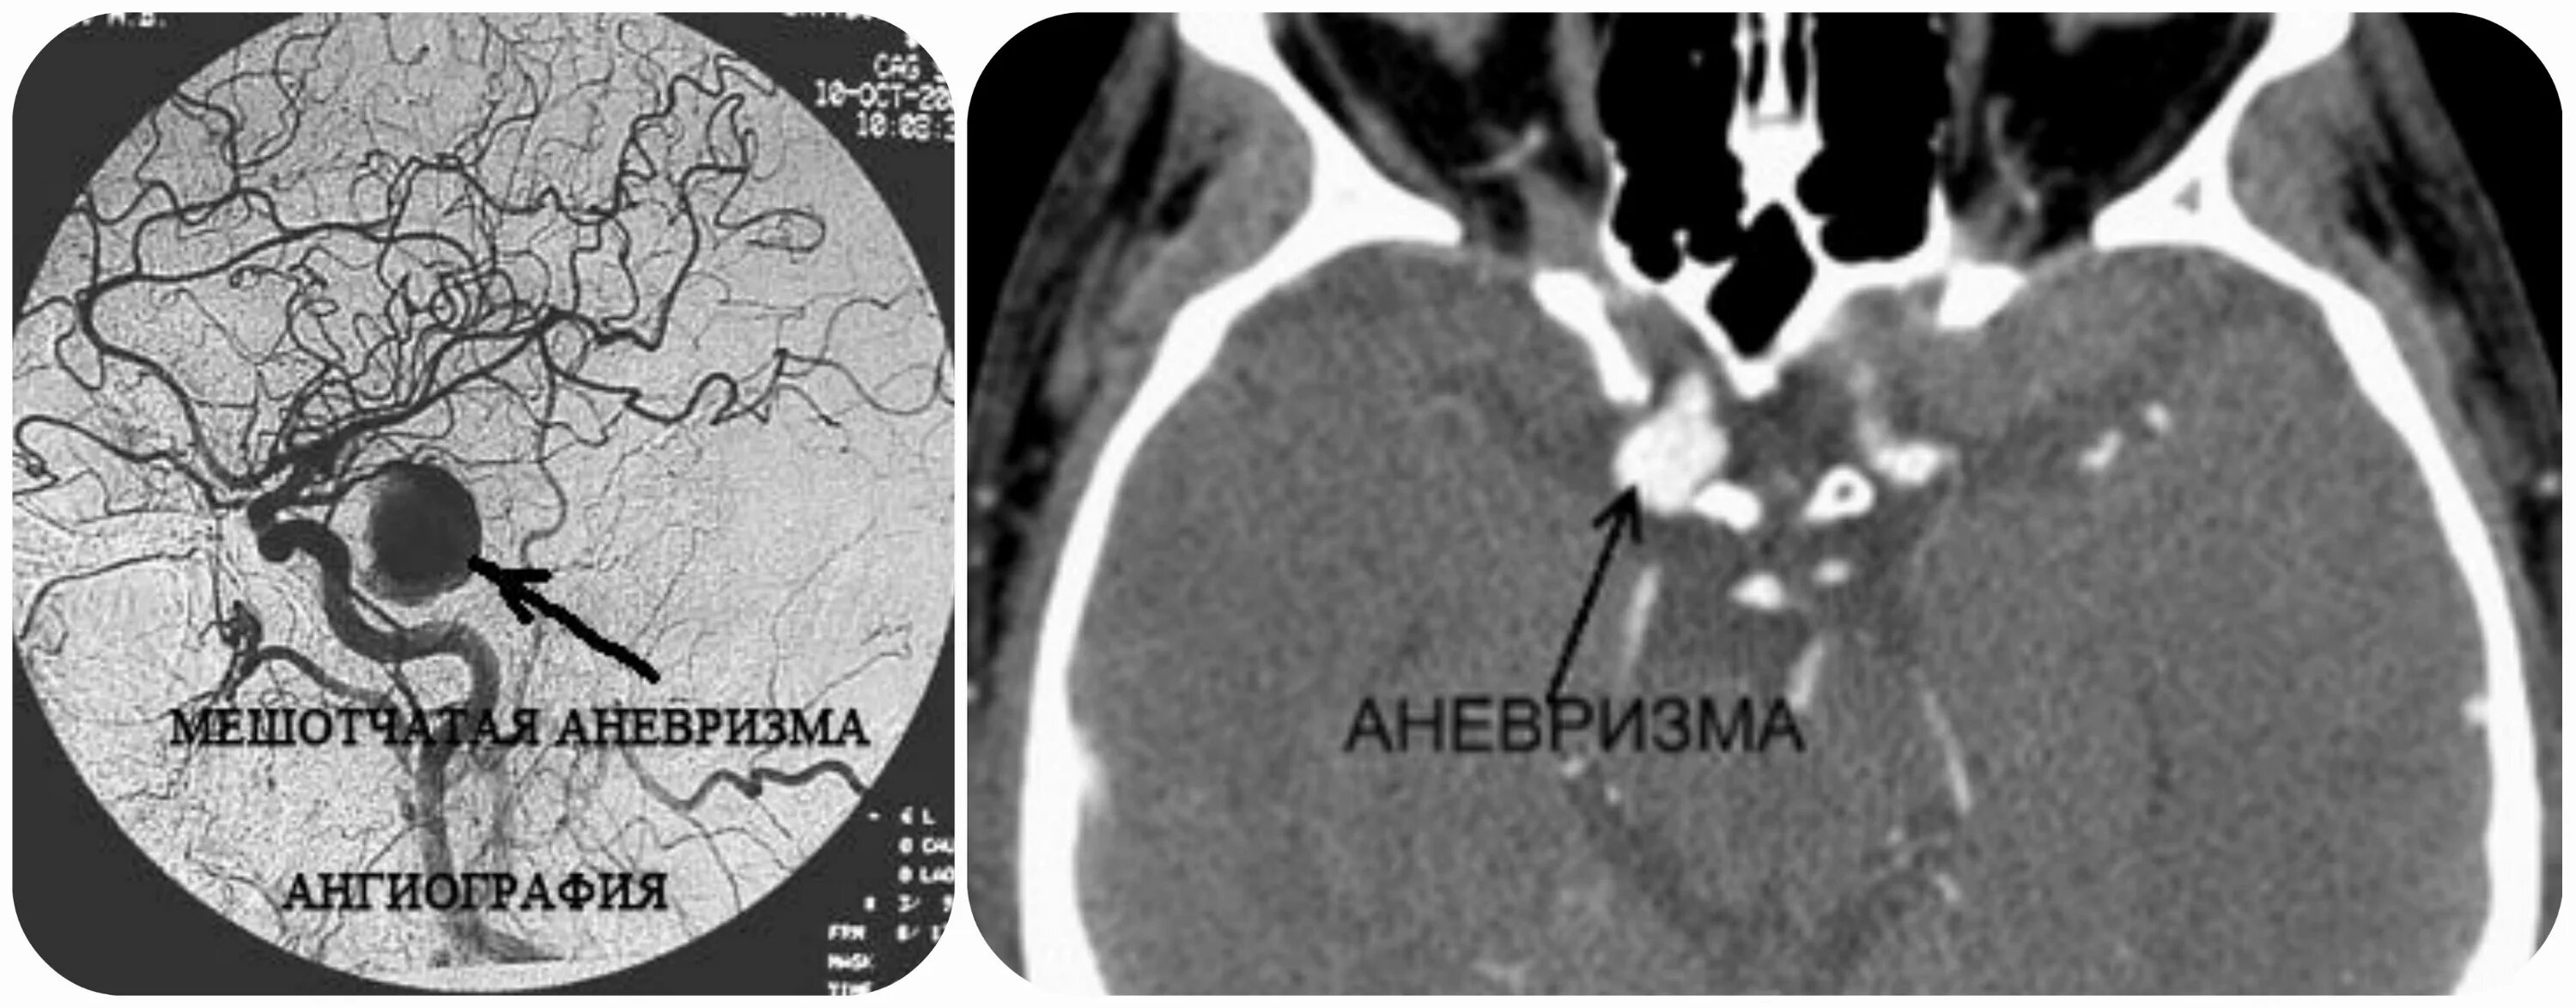

Аневризма головного мозга на кт